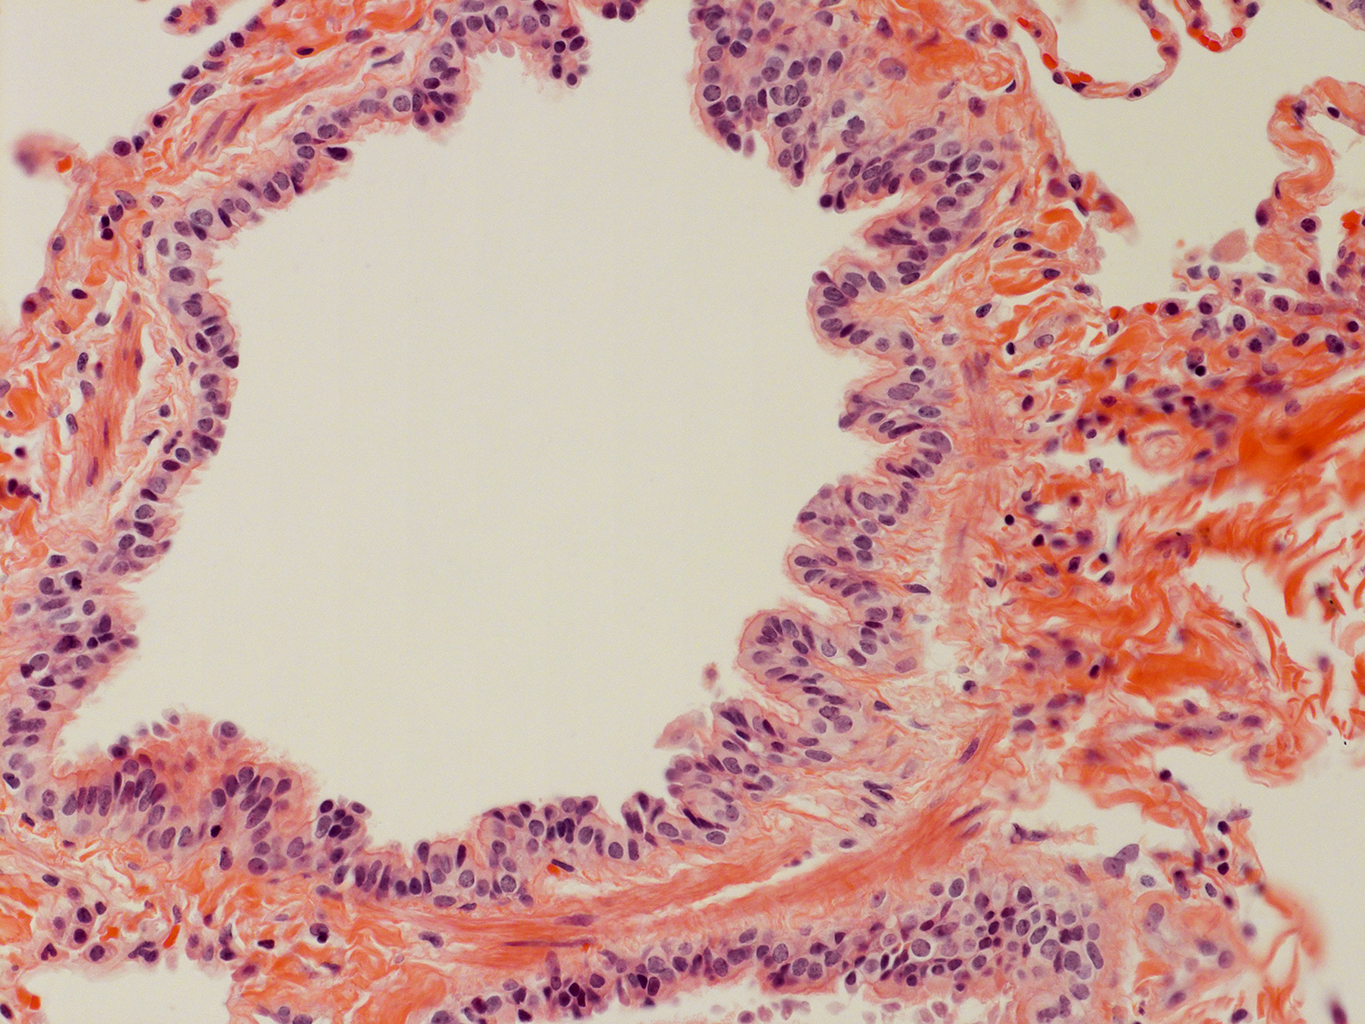

Donor tissue kindly provided by Dr. Scott Randell, University of North Carolina

Tissue Used:

LMHA-15-UNC-2017-12-19_D0037L.05HP_3_48

Gender: Male

Age:Â 43 Year Old

Race: Hispanic

Non-Smoker